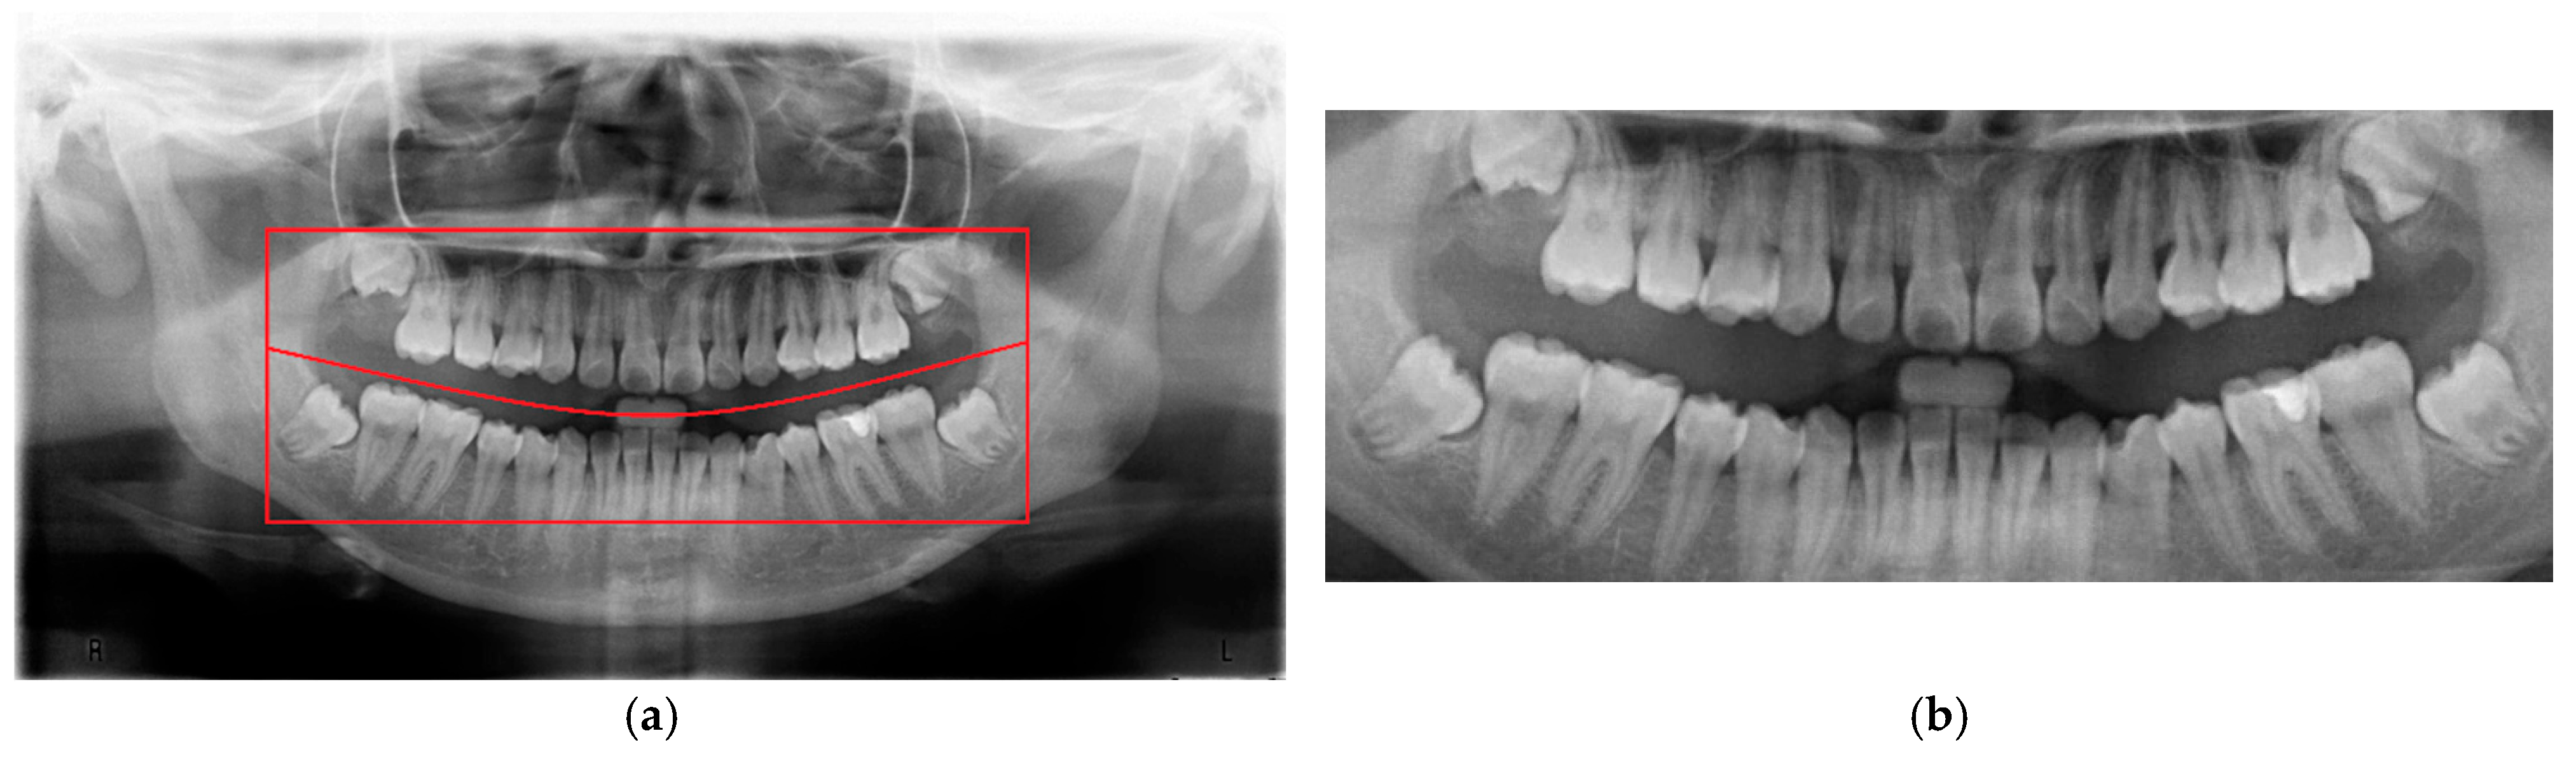

To minimize the influence of non-target regions on the recognition process, position adjustment was implemented as a critical preprocessing step. Given the variability in oral cavity positioning across different patients, the average location of the oral cavity was estimated using 100 randomly selected PANO images. Based on this analysis, the target region was determined to be approximately 625 × 1650 pixels, as shown in Figure 3. Using this reference region, only the relevant portions of each original PANO image were retained. This cropping process effectively eliminated extraneous areas outside the alveolar bone, thereby enhancing the accuracy and efficiency of the subsequent recognition tasks performed by the CNN model.

Figure 3. An example of finding the initial average block. (a) The original PANO image with the red line representing the ideal cropping line. (b) The result of position adjustment.